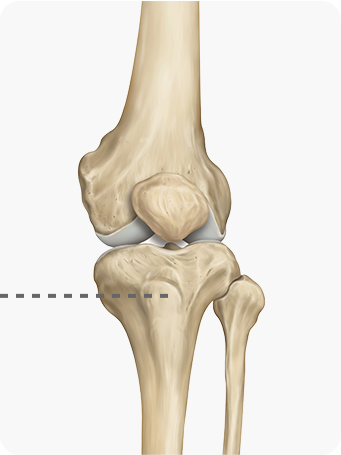

퇴행성관절염으로 연골이 마모되고 관절이 내려앉게 되어

진행된 휜 다리(O 다리, X 다리)를 바르게 교정하여

무릎 내 외측에 집중되어 있는 무게 중심을

고르게 분산시켜 관절염의 진행을 막는 수술법

입니다.

해골 이미지